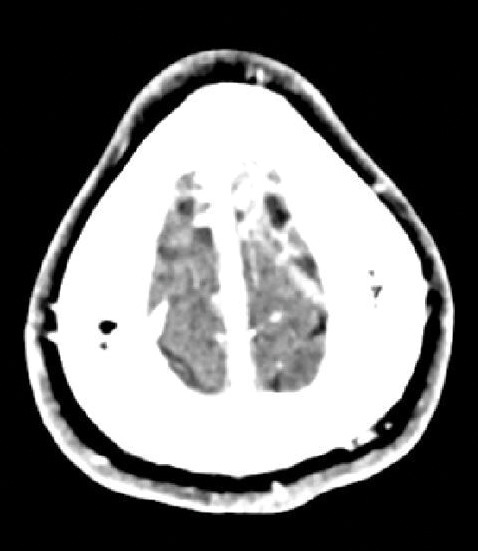

Huit jours plus tard, le patient présente un épisode de clonies du membre supérieur droit, suivi, dans la journée, d’une crise tonico-clonique généralisée, sans céphalées, nausées ni vomissements. Il s’agit du premier épisode décrit chez ce patient. Le scanner cérébral non injecté révèle une hyperdensité au niveau de la veine corticale de la convexité frontale postérieure gauche (fig. 1). L’angioscanner confirme une thrombose veineuse cérébrale (TVC), sans hémorragie ni atteinte parenchymateuse associée (fig. 2). Une relecture de l’IRM confirme l’absence d’antériorité ou de signe qui aurait pu être annonciateur d’une TVC.

L’imagerie permet de poser le diagnostic. Le scanner non injecté peut mettre en évidence des signes directs tels que l’hyperdensité spontanée d’un caillot (signe de la corde). Néanmoins, ce signe n’a pas une spécificité élevé, puisqu’il est aussi observé chez des patients atteints de polyglobulie, chez le sujet jeune avec un hématocrite élevé ou chez le ­patient déshydraté.5 L’angioscanner met en évidence un ­défaut de remplissage après injection (signe du delta vide quand le caillot est au niveau sinusal).4 L’IRM constitue l’examen de référence, en particulier pour les formes corticales et les atteintes parenchymateuses.2